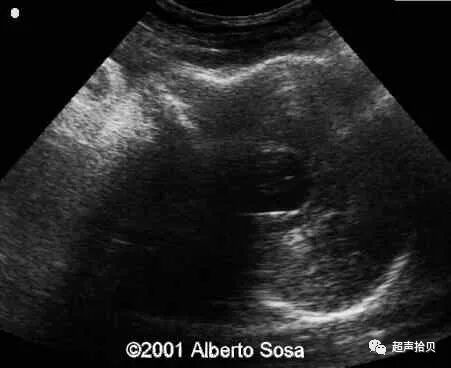

图2:冠状超声图显示位于后颅窝蛛网膜囊肿